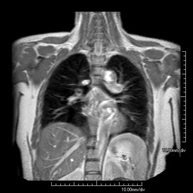

- RM del Mediastí

Prova diagnòstica no invasiva que consisteix en l'obtenció d'imatges d'alta definició anatòmica del mediastí mitjançant l'ús d'un camp electromagnètic i ones de ràdio (amb un emissor i un receptor). No utilitza radiació ionitzant. El mediastí és la part central de la caixa toràcica que inclou el tim, els grans vasos (aorta toràcica, vena cava inferior i superior, etc.), el cor, la tràquea i els bronquis principals, els ganglis limfàtics mediastínics i hilars, l'esòfag, etc. Està especialment indicada en lesions mediastíniques per diferenciar si són quístiques o sòlides, en el diagnòstic diferencial de les lesions del mediastí anterior, etc. De vegades s'ha d'emprar contrast paramagnètic (Gadolini) per completar l'estudi. - RM Tòrax

Prova diagnòstica no invasiva que consisteix en l'obtenció d'imatges d'alta definició anatòmica del tòrax mitjançant l'ús d'un camp electromagnètic i ones de ràdio (amb un emissor i un receptor). No utilitza radiació ionitzant. Està indicada en aquelles lesions pulmonars en les quals s'ha de descartar si hi ha infiltració del mediastí o de la paret toràcica, per diferenciar si una lesió toràcica és sòlida o quística, etc. En alguns casos caldrà emprar contrast paramagnètic (Gadolini) per completar l'estudi. - RM de Paret Toràcica